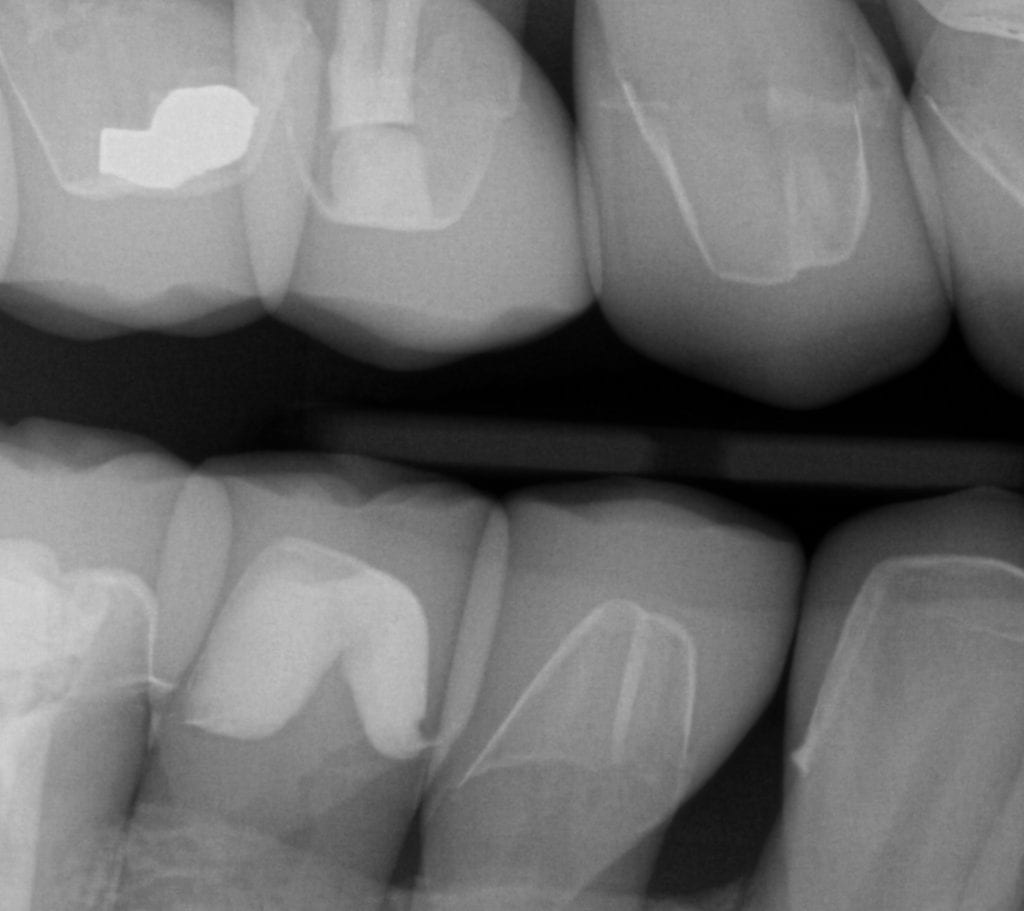

ONE WEEK POST-OP RADIOGRAPHS / CEMENT CHECK